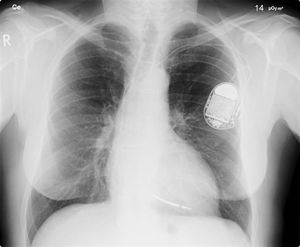

إن معظم منظمات ضربات القلب تركب في الجزء الأعلى من الصدر من خلال عملية تستغرق حوالي ساعة واحدة تجرى تحت تأثير التخدير الموضعي فقط، حيث يقوم الطبيب المختص بعمل فتحة صغيرة في الجلد ومن ثم يتم إدخال المنظم تحت الجلد بعد إتمام عملية توصيل السلك الكهربائي في المكان الخاص به بالقلب عن طريق الأوردة ومن ثـم يتـم إغلاق هذه الفتحة بالخيوط الجراحية.

وأثناء عملية التركيب هذه يقوم الطبيب بمراقبة حركة السلك من خلال شاشة تلفزيونية تحت الأشعة السينية لوضع السلك الكهربائي في مكانه المحدد بالقلب.